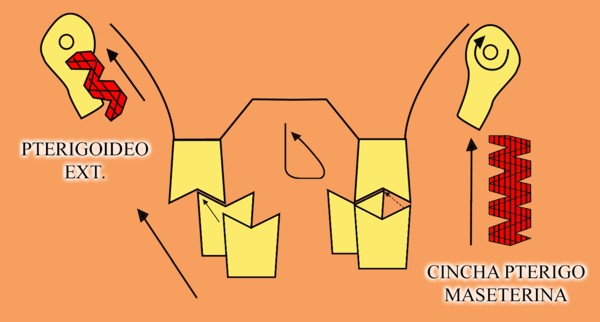

En un esquema de lateralidades a la izquierda, observamos que el Fulcrum de la misma lo encontramos en el cóndilo izquierdo, Cóndilo de Trabajo, la Potencia se encuentra en la fuerza generada por el Pterigoidéo Ext. del lado derecho, Cóndilo de No Trabajo, y la resistencia se dispone, en el caso de una FUNCIÓN DE GRUPO, en las Crestas Triangulares Internas de la tabla premolar-molar superior, que rozan contra las Crestas Centrales antagonistas ,correspondientes al inferior.

Por lo tanto, el Brazo de Potencia se establece entre el CnT(POTENCIA),y el CT(Fulcrum), mientras que los Brazos de Resistencia de las distintas piezas que intervienen en la Función de Grupo, se encuentran entre estas piezas y el CT(Fulcrum).

Como podemos ver en el esquema, estos son menores que el Brazo de Potencia y por lo tanto la fuerza generada por el mismo, producirá mayor deterioro , pues la palanca no está equilibrada:

EL BRAZO DE POTENCIA ES MAYOR QUE EL DE RESISTENCIA (Fig.6)

Sabemos que la fuerza desarrollada por el Pterigoideo Int. y el Masetero, músculos elevadores por excelencia, manifiestan durante el acto masticatorio su máxima expresión(LT), por lo tanto es evidente que dichas fuerzas soportadas fuera del eje axial de la pieza ,determinan grandes daños para las estructuras de soporte.